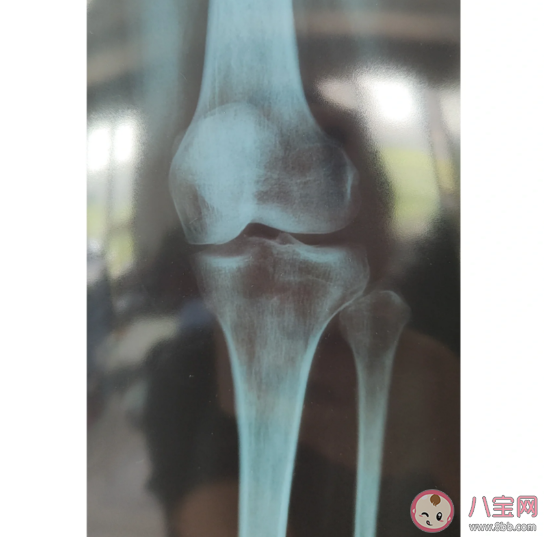

骨刺在医学上被称为骨质增生,它的产生本质上是身体的一种“自我保护”。骨刺的形成“非一日之寒”,它通常是伴随身体衰老而产生的。一些年轻人常常久坐久站、姿势不良、缺乏运动等,同样会长出骨刺,外伤、肥胖、内分泌紊乱、骨细胞代谢异常、关节局部血液循环改变等也是诱因。

若骨刺尺寸较大或长在特殊部位,会影响邻近的神经、血管或关节,从而导致肿胀、疼痛、发麻、行走无力或不稳、关节伸直或弯曲受限等症状。